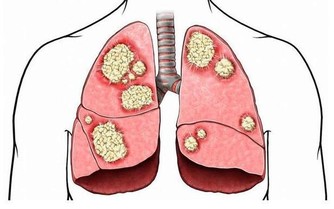

當我們談到有關女性的癌症類型時,你必然會提起乳腺癌,因為這是女性發病率最高的癌症。然而與此同時,大家一定不要忘了卵巢癌,這也是一名同樣危險的殺手,發病率也相當高。

而且,卵巢上皮癌死亡率,佔各類婦科腫瘤的首位。其死亡率如此之高,重要原因是很難早期發現。我們身邊會有一些女性知道對乳房進行自檢,卻不知道關注卵巢癌的跡象。

這其實也不能怪大家不重視,的確存在客觀原因,因為卵巢在身體深處,即使長了腫瘤也很難被感知到。即使身體用疼痛來提醒你,也往往會被當作普通的肚子痛。

那麼,卵巢癌都有哪些比較典型的症狀呢?很遺憾,並沒有那樣一個確定的信號,讓我們一看到就知道這個人患了卵巢癌。但好消息是,如果一名女性罹患卵巢癌,會有一個症狀比較突出,那就是“尿頻”,然而根據英國慈善機構的調查結果,大約只有百分之一的人知道經常需要排尿是卵巢癌的症狀。

原因很簡單,因為卵巢那里長了不該長的東西,也就是腫瘤,這個東西是有體積的,隨著它迅速長大,要獲取生長空間,就會去擠壓周圍的器官,包括膀胱。你的膀胱總是被壓迫,讓它誤以為自己需要尿尿。

但重要的是,你要意識到自己的尿頻可能意味著更嚴重的可能性,特別是如果你正在經歷卵巢癌的其他常見症狀,如腹脹、食慾減退或骨盆和/或腹痛。如果你的尿頻與任何這些症狀同時出現,最好盡快看醫生。